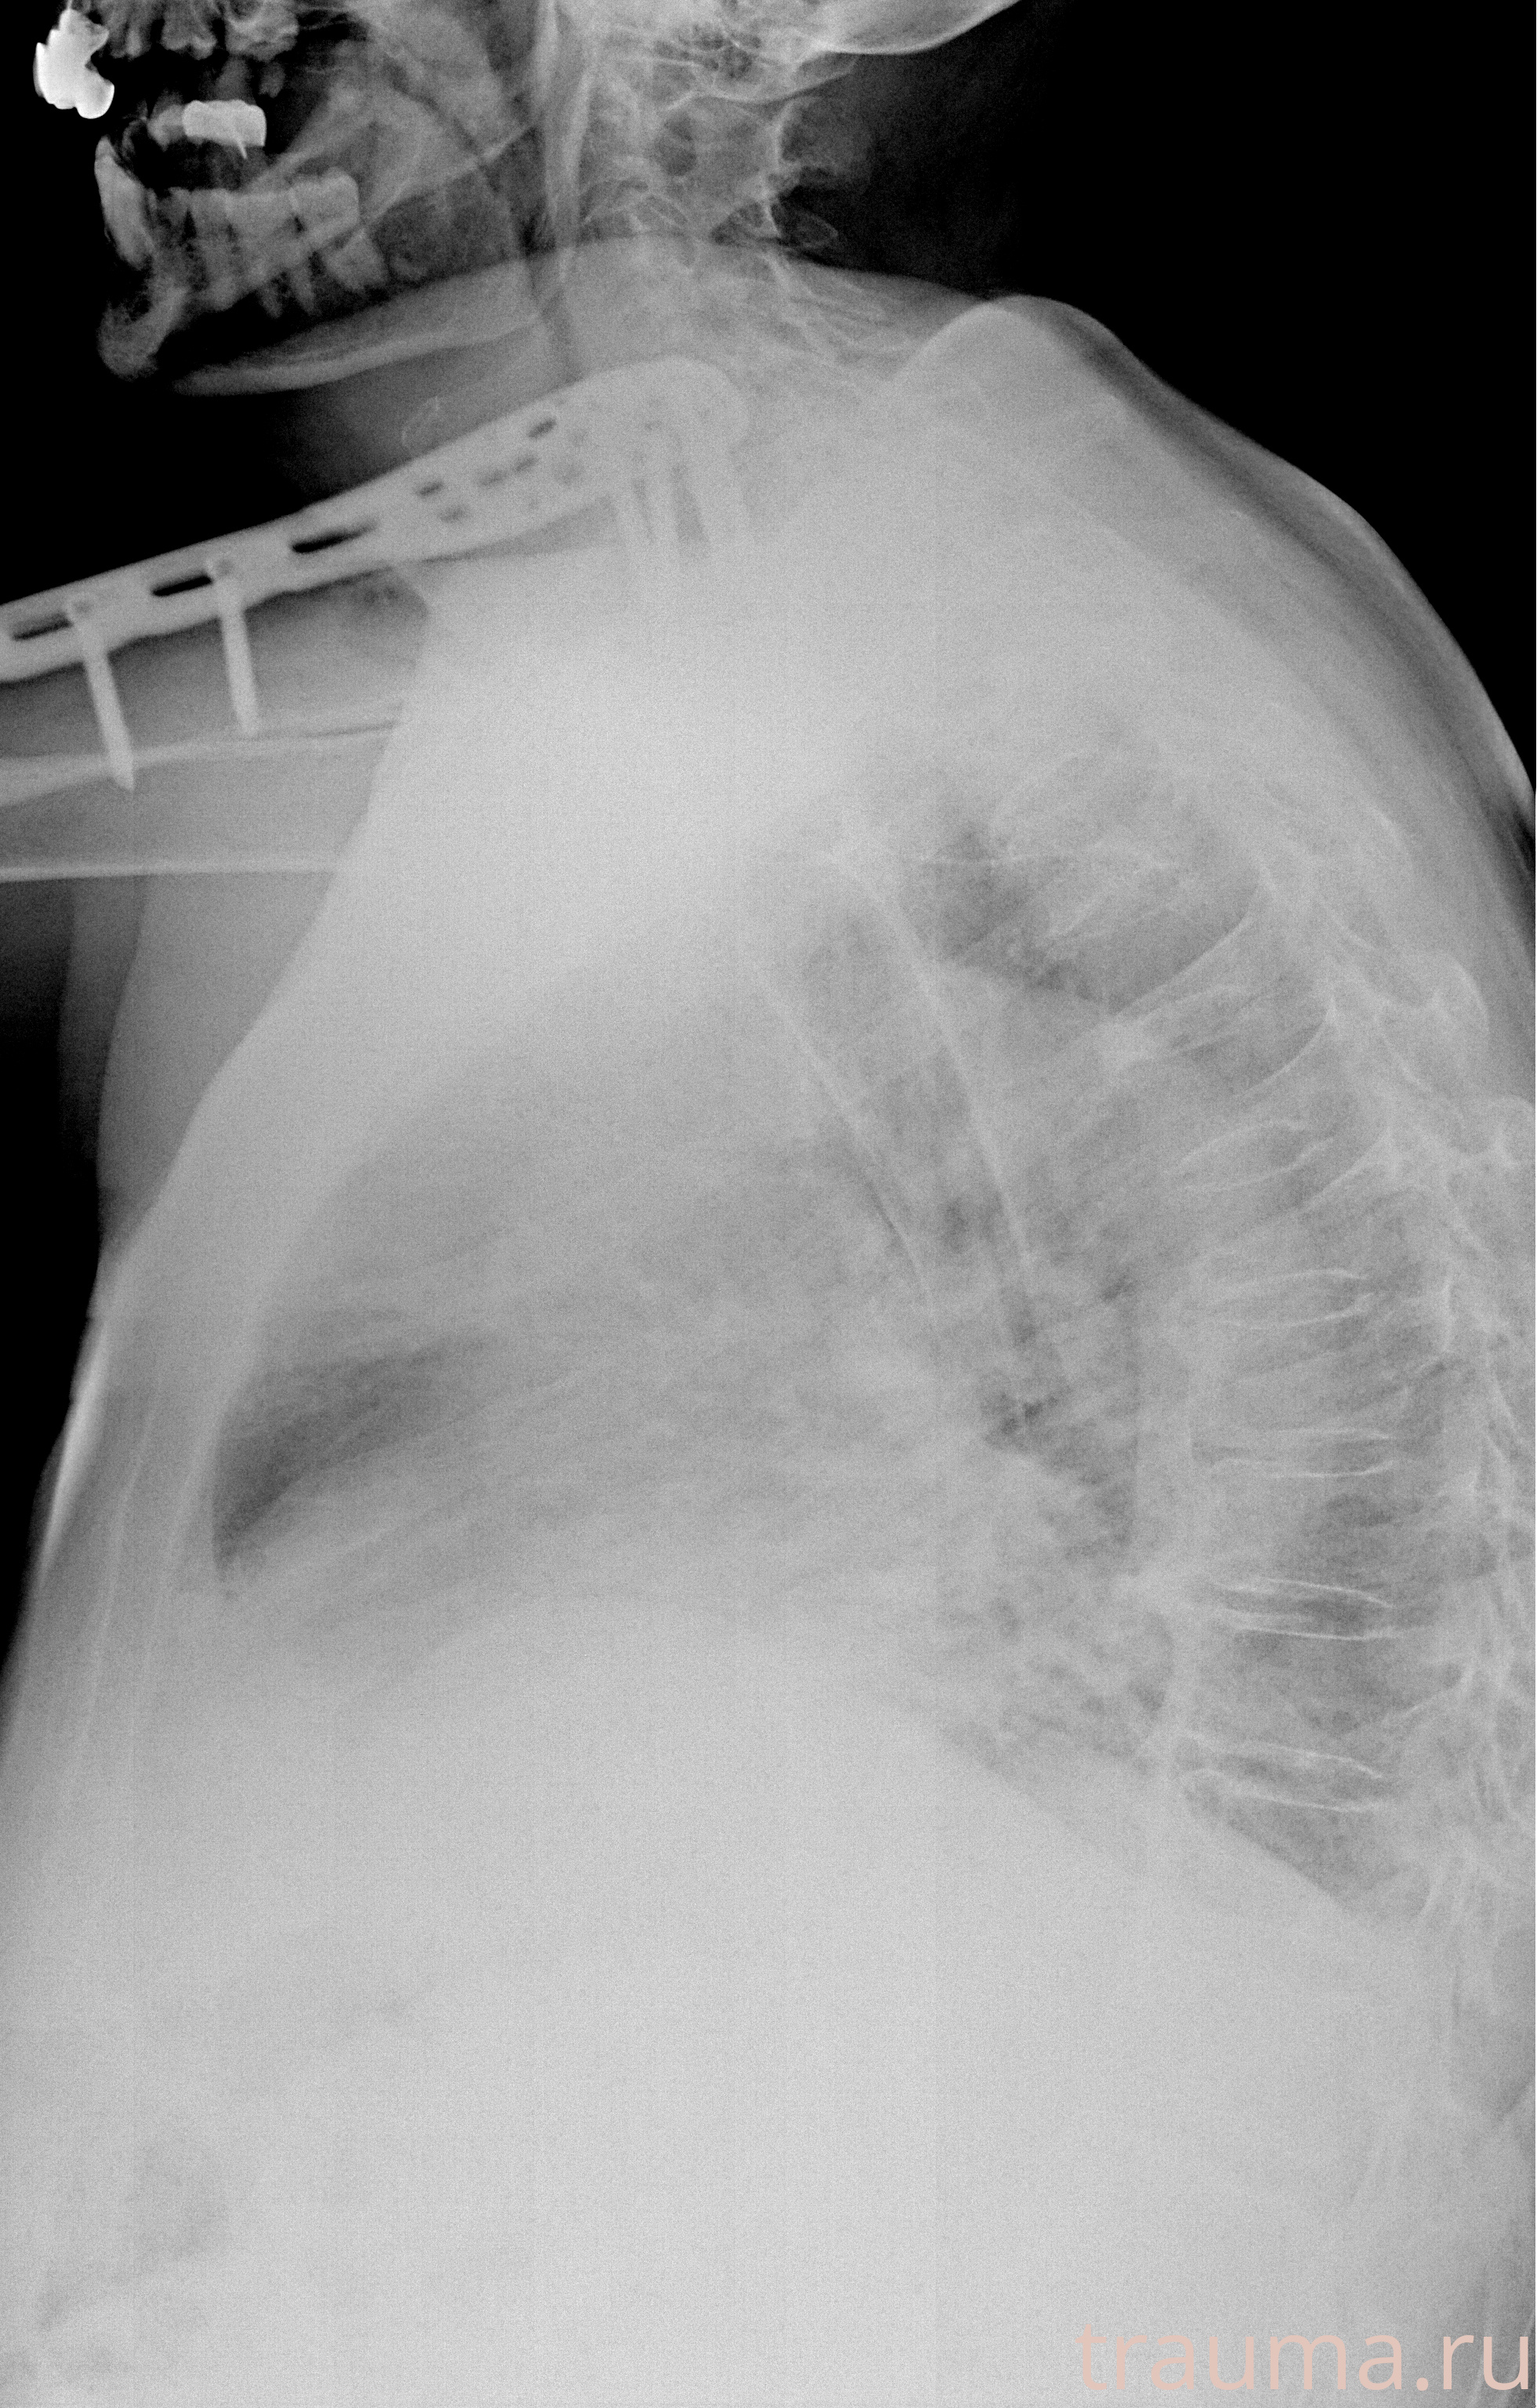

Рентгенограммы

Рентген на дому: по вашему адресу приезжает врач-рентгенолог, травматолог-ортопед с мобильным рентгеновским аппаратом, проводит диагностику травмы или заболевания, делает необходимые рентгенограммы, дает рекомендации по дальнейшему лечению. Получить качественные снимки в домашних условиях возможно благодаря уникальной методике, разработанной МосРентген Центром для института  Склифосовского

при переломе шейки бедра и пневмонии от компании МосРентген Центр - партнера Института имени Склифосовского